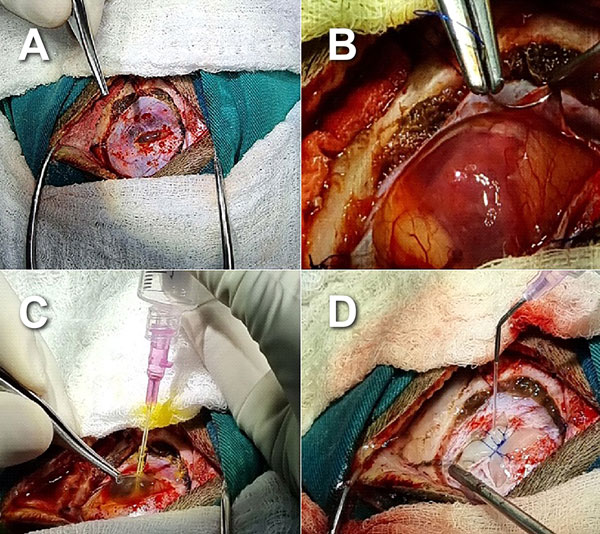

Intervención

Se planificó tratamiento quirúrgico y se realizó craneotomía temporal izquierda, apertura dural e identificación de la lesión tumoral; se procedió a punción directa del quiste intratumoral en la que se obtuvieron, aproximadamente, 10 ml de un líquido amarillento. Mediante técnica microquirúrgica se identificó el nódulo tumoral y se hizo resección completa; no se resecó la cápsula tumoral ya que esta era muy fina y en algunos sectores era indistinguible del tejido cerebral (Figura 2).

Figura 2. Imágenes transquirúrgicas. A) Durotomía. B) Aspecto quístico de lesión posterior a durotomía. C) Punción directa del quiste y obtención de líquido intratumoral amarillento. D) Duroplastia al finalizar exéresis tumoral.